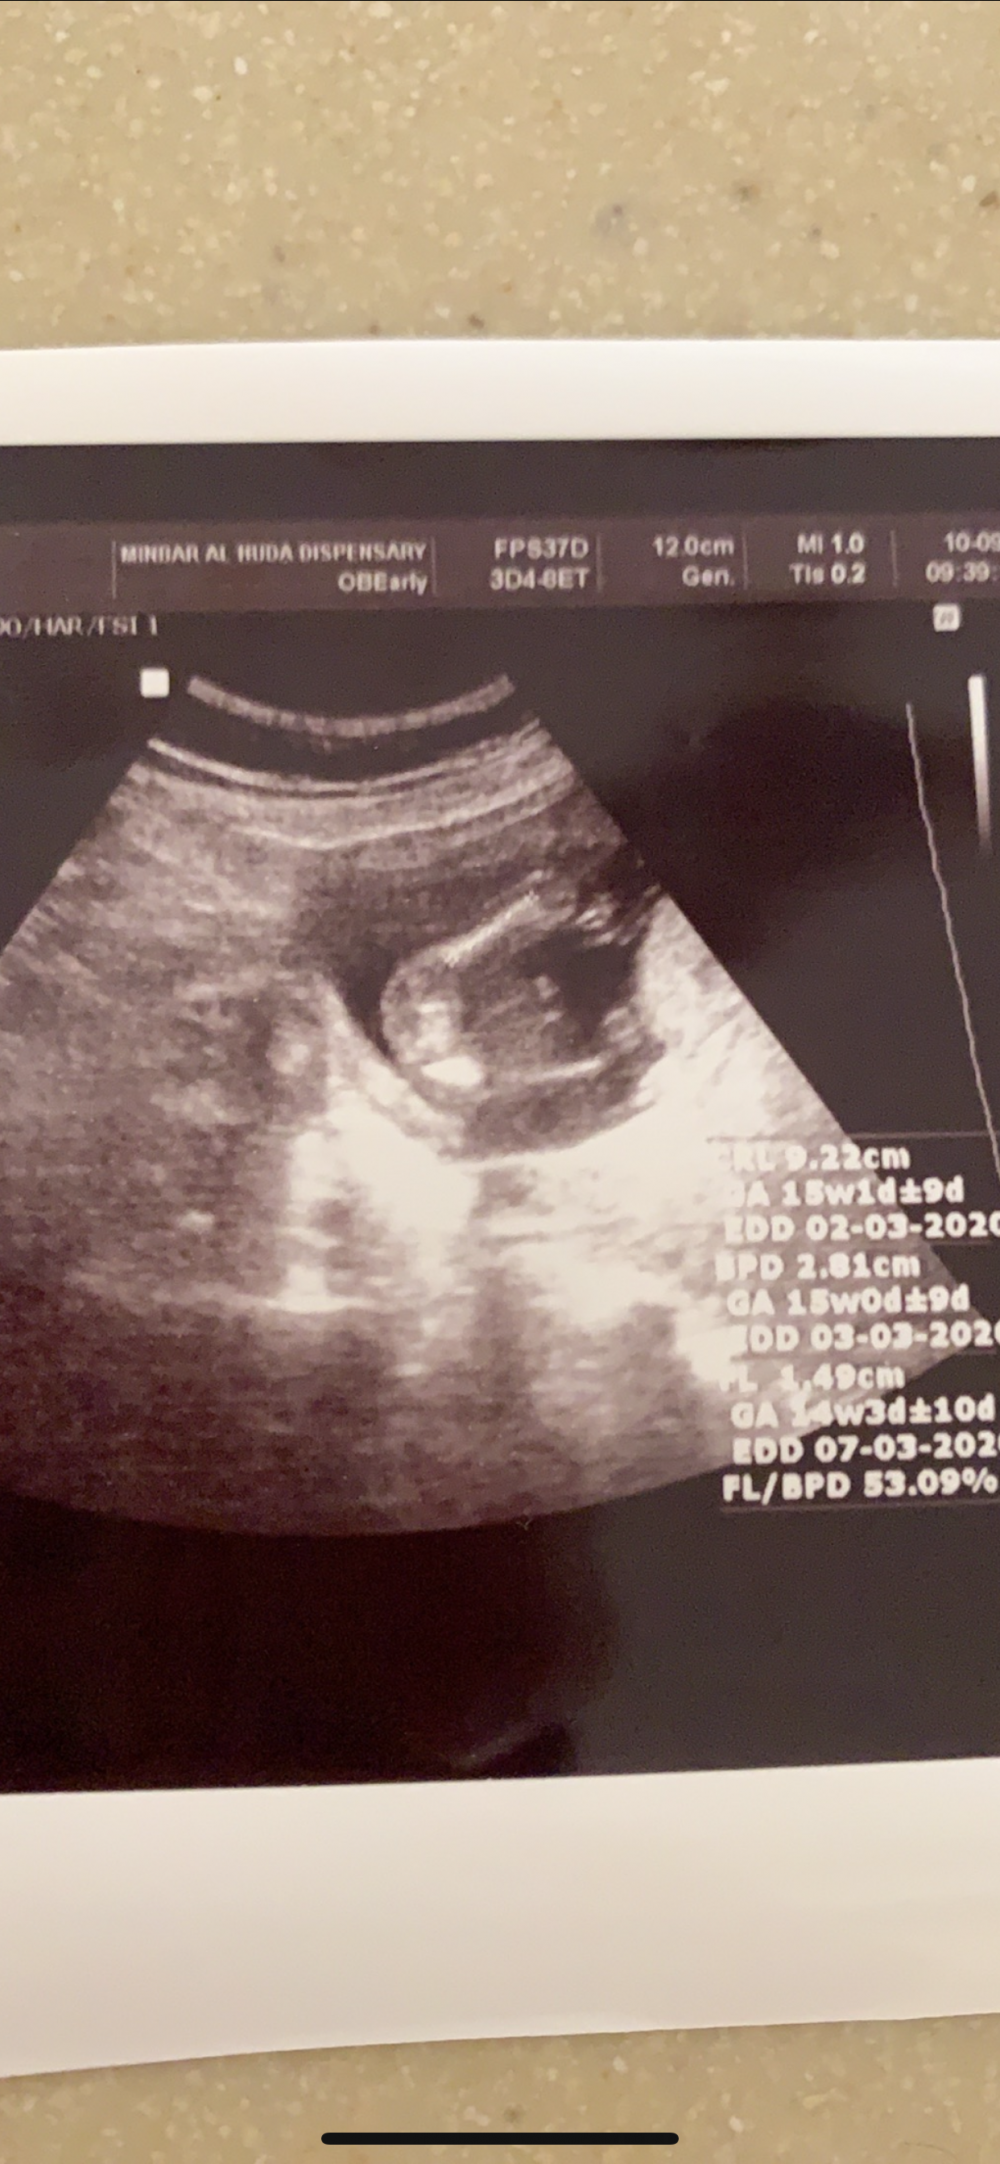

لان بصورة السونار صاير مو واضح انها بنت مااشوف فيه ٣خطوط

امين يارب لان بصورة السونار صاير مو واضح انها بنت مااشوف فيه ٣خطوط